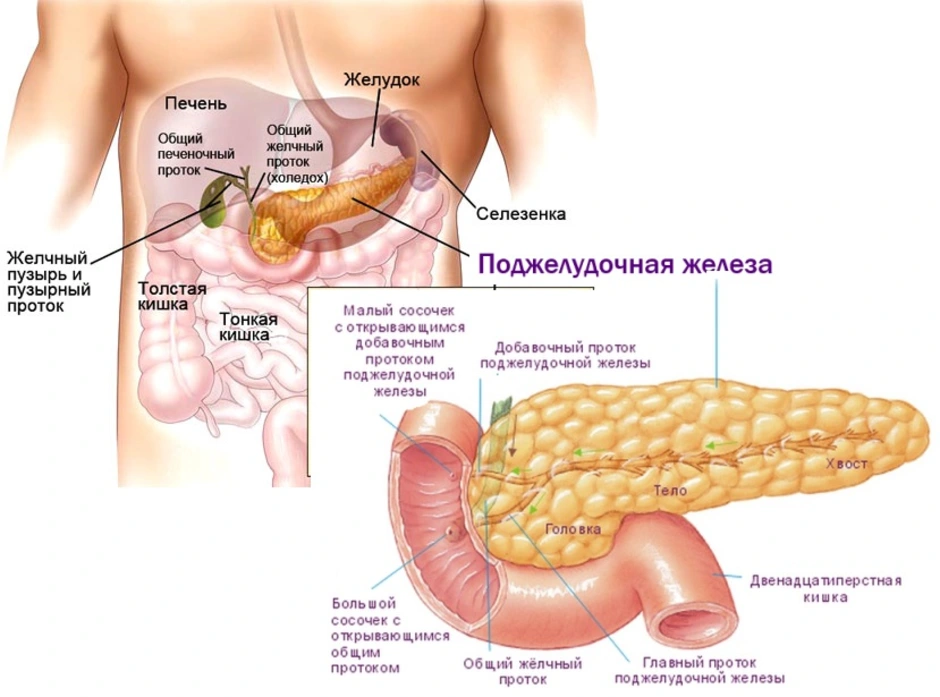

УЗИ диагностика кольцевидной поджелудочной железы: что важно знать